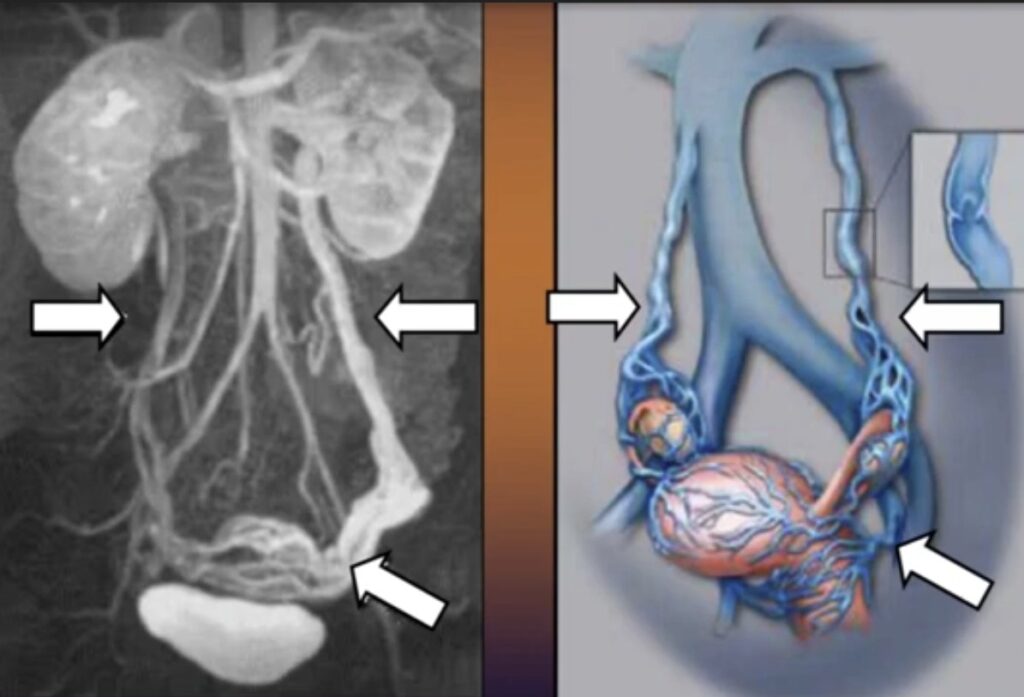

L’embolizzazione del varicocele pelvico è una procedura di radiologia interventistica che consente di trattare la congestione venosa in modo mininvasivo e mirato.

Attraverso un accesso venoso percutaneo, il radiologo interventista raggiunge le vene patologiche e le occlude selettivamente, eliminando il reflusso responsabile dei sintomi.

- cateterismo selettivo delle vene ovariche e pelviche

- embolizzazione mediante spirali metalliche e/o agenti sclerosanti